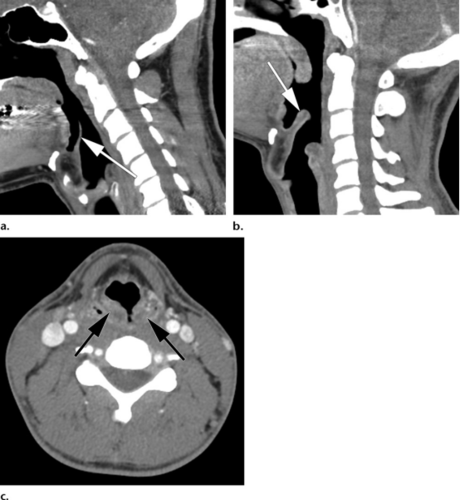

颈椎ct提示颈4-5,5-6椎间盘突出,后纵韧带钙化

医影精品颈部ct影像分析及急诊报告要点

颈椎腰椎ct常见病变

正常颈椎ct图片图解

颈椎ct图片图解

颈椎病ct图片讲解

颈椎ct讲解图

颈椎ct图片片子

颈椎ct图片

颈椎ct

颈椎ct三维重建

颈椎ct报告